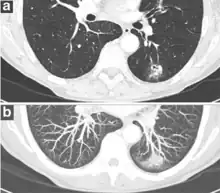

- In case of subsolid nodules, being part solid has a higher risk of cancer than being purely ground glass opacity.

Part solid nodule.[9]

Ground glass opacity nodule.[9]